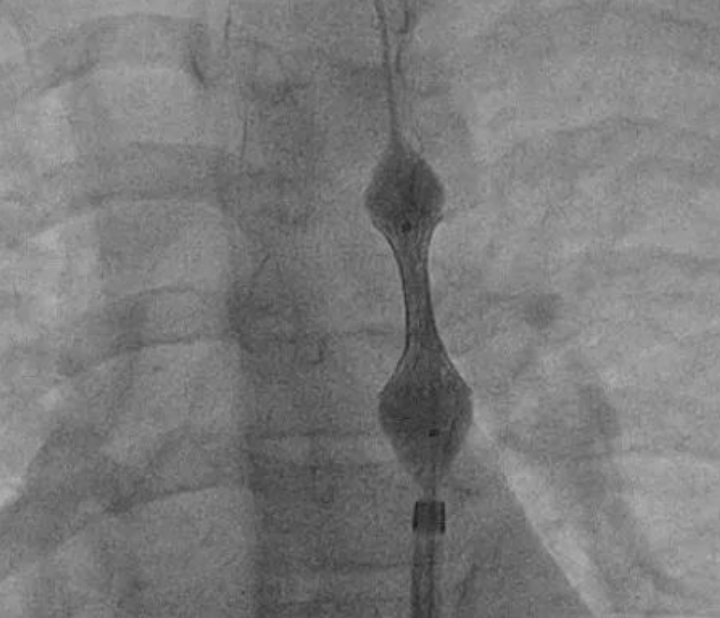

从产品名称中可以窥探其一二,巧克力球囊当然不是我们平常吃的巧克力,而是其外形与块状巧克力类似,都有凹凸不平的类似波浪形的外观,类似有波峰和波谷的结构;

在球囊的外表面加了一层镍钛记忆合金约束性金属网状结构,球囊在金属网的约束下可控、均匀和无创伤的扩张。

特点:1)通过枕部施加压力,提供可控扩张以达到有效扩张的目的;2)凹槽减轻应力作用,阻止夹层扩展延伸,从而降低血管夹层的发生概率;3)卸压速度快并具有优异的回抱性能,降低二次通过外径,有利于球囊使用多次后仍然能通过钙化病变;4)在球囊扩张过程时,减少球囊沿轴向扩张的程度,从而降低对非病变血管的损伤;5)在偏心钙化病变中球囊依然能够均匀扩张,减少“狗骨头效应”。

狗骨头效应图

狗骨头效应图2.1.2 Chocolate Touch:球囊+金属网状结构+紫杉醇药物